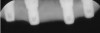

Interceptive implant therapy may then become a consideration earlier in life to create restorations that will not be subject to the latent effect of dental caries as aging continues. An example is shown in Figure 6 and Figure 7; the panoramic film of a 56-year-old man shows several orthognathic and extensive dental procedures historically. All full-coverage restorations had been replaced for a second time, and, again, all evidenced recurrent caries, but the existing dentition was periodontally sound and relatively esthetic.

Fig 6. Panoramic radiograph of 56-year-old patient illustrating a number of dental procedures historically.

Figure 6

Fig 7. Existing dentition was sound periodontally and reasonably esthetic.

Figure 7